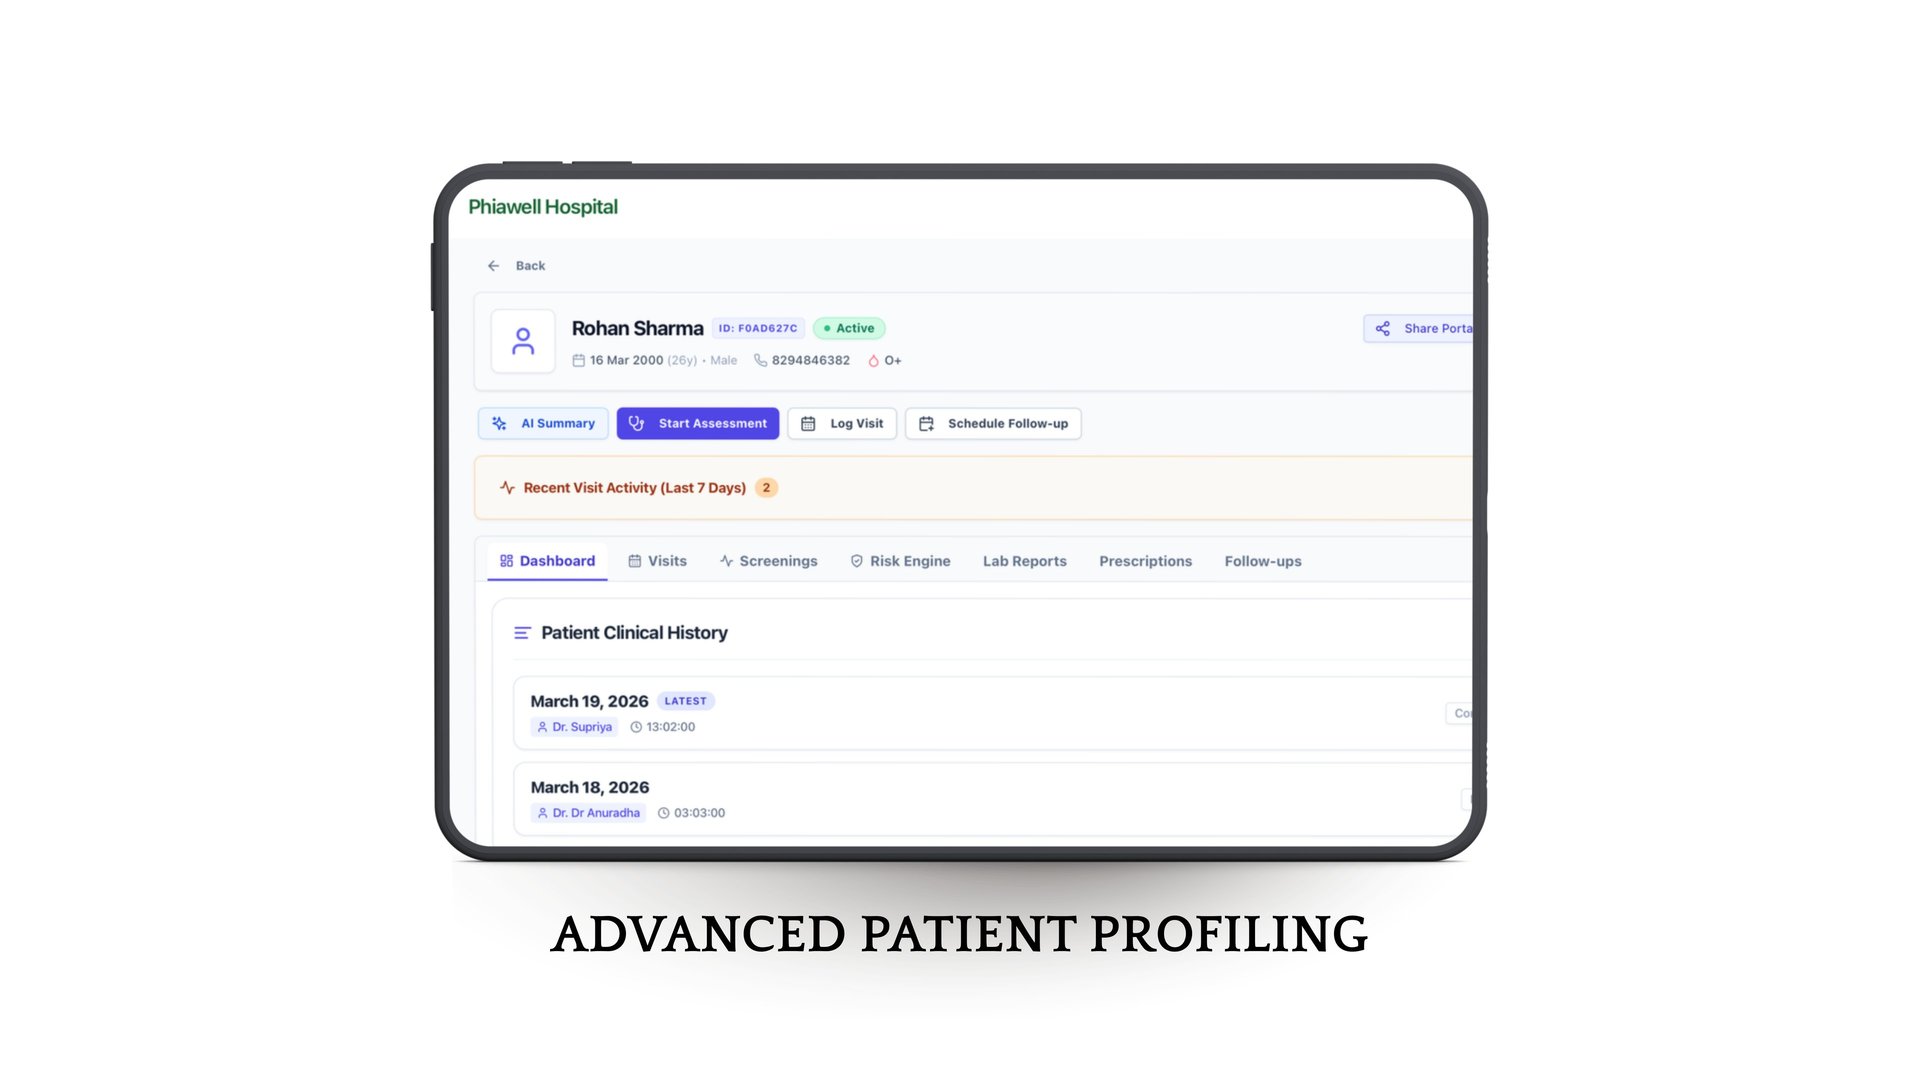

We empower Doctors, clinics and hospitals with our technology-enabled platform, enabling efficient and structured patient management through single account and health risk evaluations at the OPD level.

It simplifies everything—from patient entry to follow-up

AI assisted health summaries & prescription writing

From better tracking to personalized care journeys, Phia.Care helps deliver a smoother, more connected experience for every patient.

Intelligent Health Insights

With built-in risk assessment, smart analytics, and concise patient summaries, doctors can make faster, more accurate decisions while shifting towards preventive care.

Phia.Care brings all patient data—visits, prescriptions, reports, and history—into one seamless platform, reducing manual work and saving time.